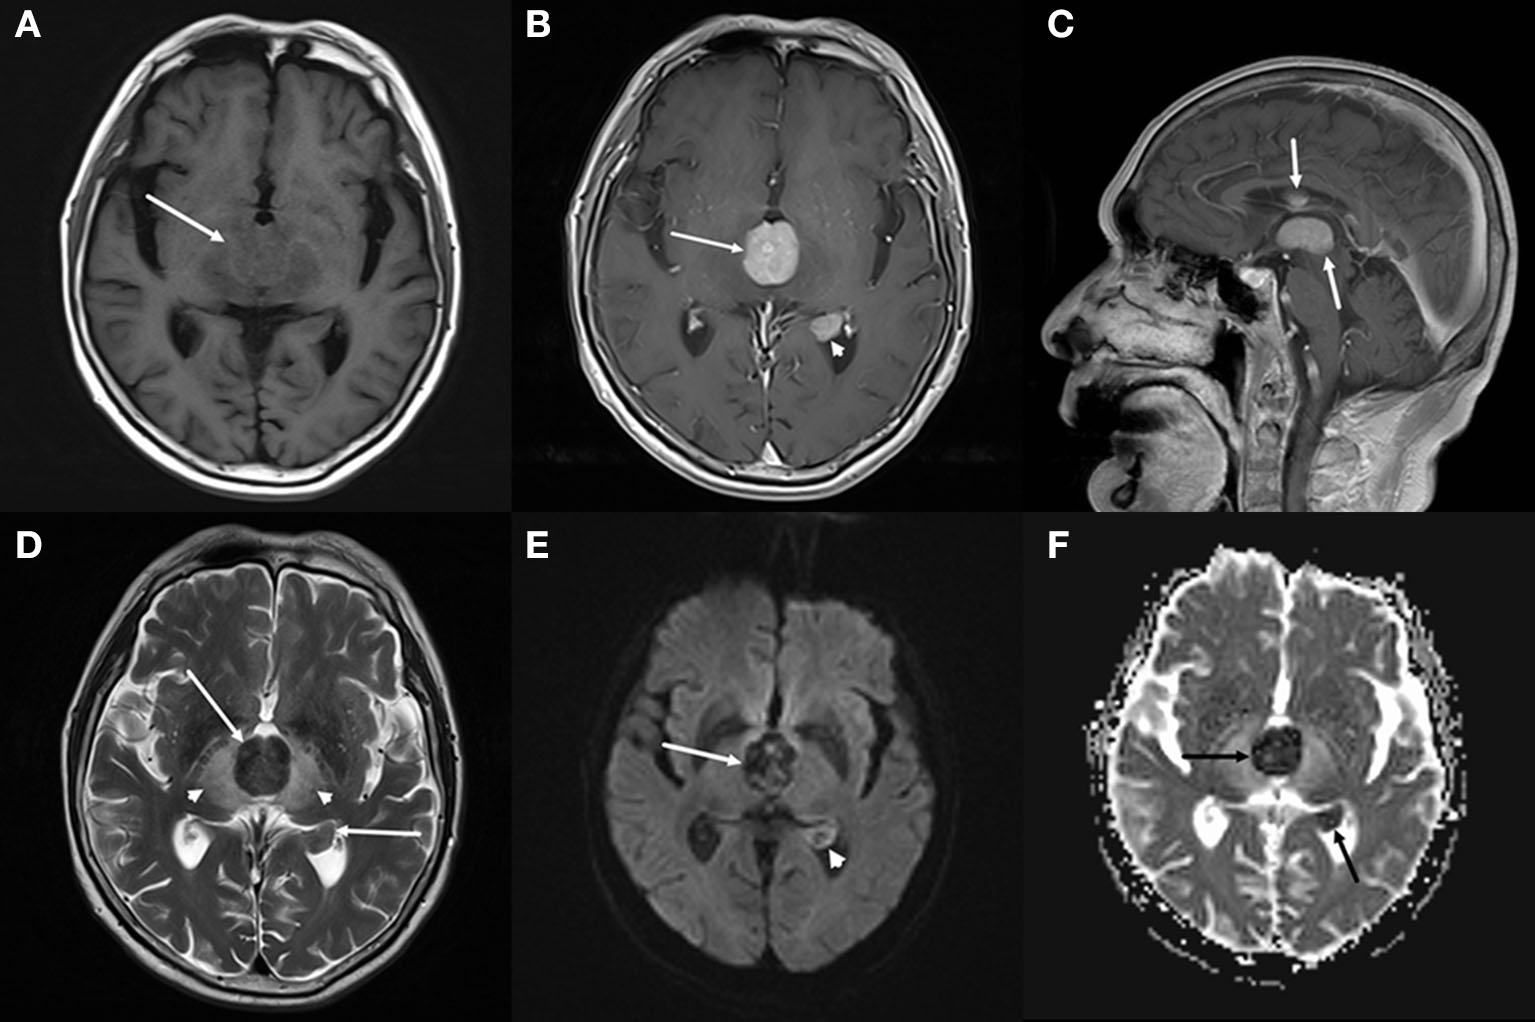

The brain computed tomography (CT) disclosed three solid masses with slight hyper-attenuation, non-calcification, and non-cystic components. The biggest one was located in the third ventricle and the others were located in the body and posterior horn of the left lateral ventricle (Figure 1), MRI showed multifocal solid lesions in the same regions. They were slightly hypointense on T1WI and isointense to slightly hypointense on T2WI and T2WI dark-fluid images. While on diffusion-weighted imaging (DWI), the third ventricular lesion was hypointense, and the lateral ventricular lesion was slightly hyperintense, both of them with low apparent diffusion coefficient (ADC) values, all suggesting diffusion restricted. Post-enhanced, the ventricular lesions were significantly enhanced. Furthermore, parenchyma around the third ventricle displayed swelling and hyperintense on T2WI. It did not cause ventricular expansion and hydrocephalus above the lesions (Figures 2A–F). He was diagnosed with intraventricular malignancy and based on his history of prostate cancer, the possibility of metastasis was considered clinically.

Figure 2

Brain magnetic resonance imaging (MRI). (A–C) Axial T1-weighted imaging (T1WI) (A) shows that the masses with slight hypointensity are in the third ventricle (arrow) and the posterior horn of the left lateral ventricle. Both of them are significantly enhanced on axial (B) and sagittal (C) T1WI with contrast. (D–F) T2-weighted imaging (T2WI) (D) shows the isointense to slightly hypointense masses (arrows), the swollen and hyperintense parenchyma around the third ventricle (arrowheads). Diffusion-weighted imaging (DWI) (E) shows a hypointense mass in the third ventricle (arrow) and a slightly hyperintense mass in the lateral ventricle (arrowhead), both of them with low apparent diffusion coefficient (ADC) value (ADC value: 0.425 × 103mm2/s, 0.628 × 103mm2/s) (F, arrow), all suggesting diffusion restricted.